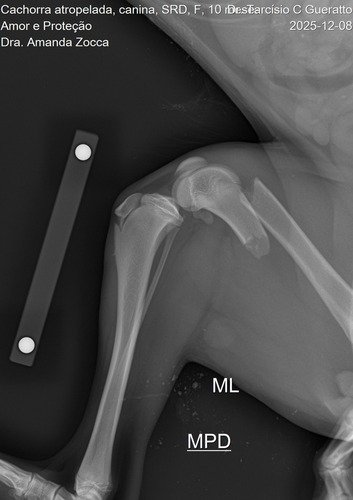

Ela teve uma fratuta grave e precisou de uma cirurgia, graças a Deus os veterinários nos cobrou metade do valor da cirurgia.